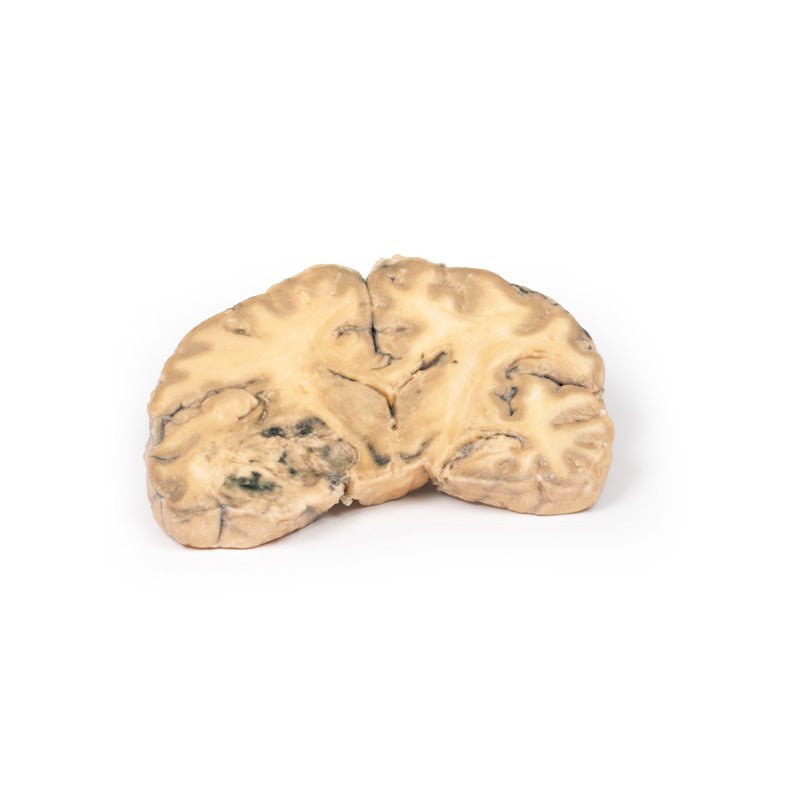

3D Printed Astrocytoma

Clinical History

A 73-year-old female was admitted with new left-sided hemiplegia. On further questioning she

revealed a 3-month history of headaches, nausea and deteriorating balance. CT brain revealed an inoperable brain

tumour. She died 1 week after being admitted.

Pathology

This brain specimen is a coronal section. In the right temporal lobe, a poorly demarcated tumour is

present. There is enlargement of the hemispheres and flattening of the gyral pattern. From the posterior aspect

of the specimen subfalcine herniation* is appreciated and the tumour appear less well differentiated with

haemorrhagic and necrotic foci. Histology of this tumour showed an astrocytoma, Grade III/IV.

*In subfalcine

(or cingulate) herniation, the most common type of brain herniation, the innermost part of the frontal lobe is

pushed under part of the falx cerebri, between the two hemispheres of the brain.